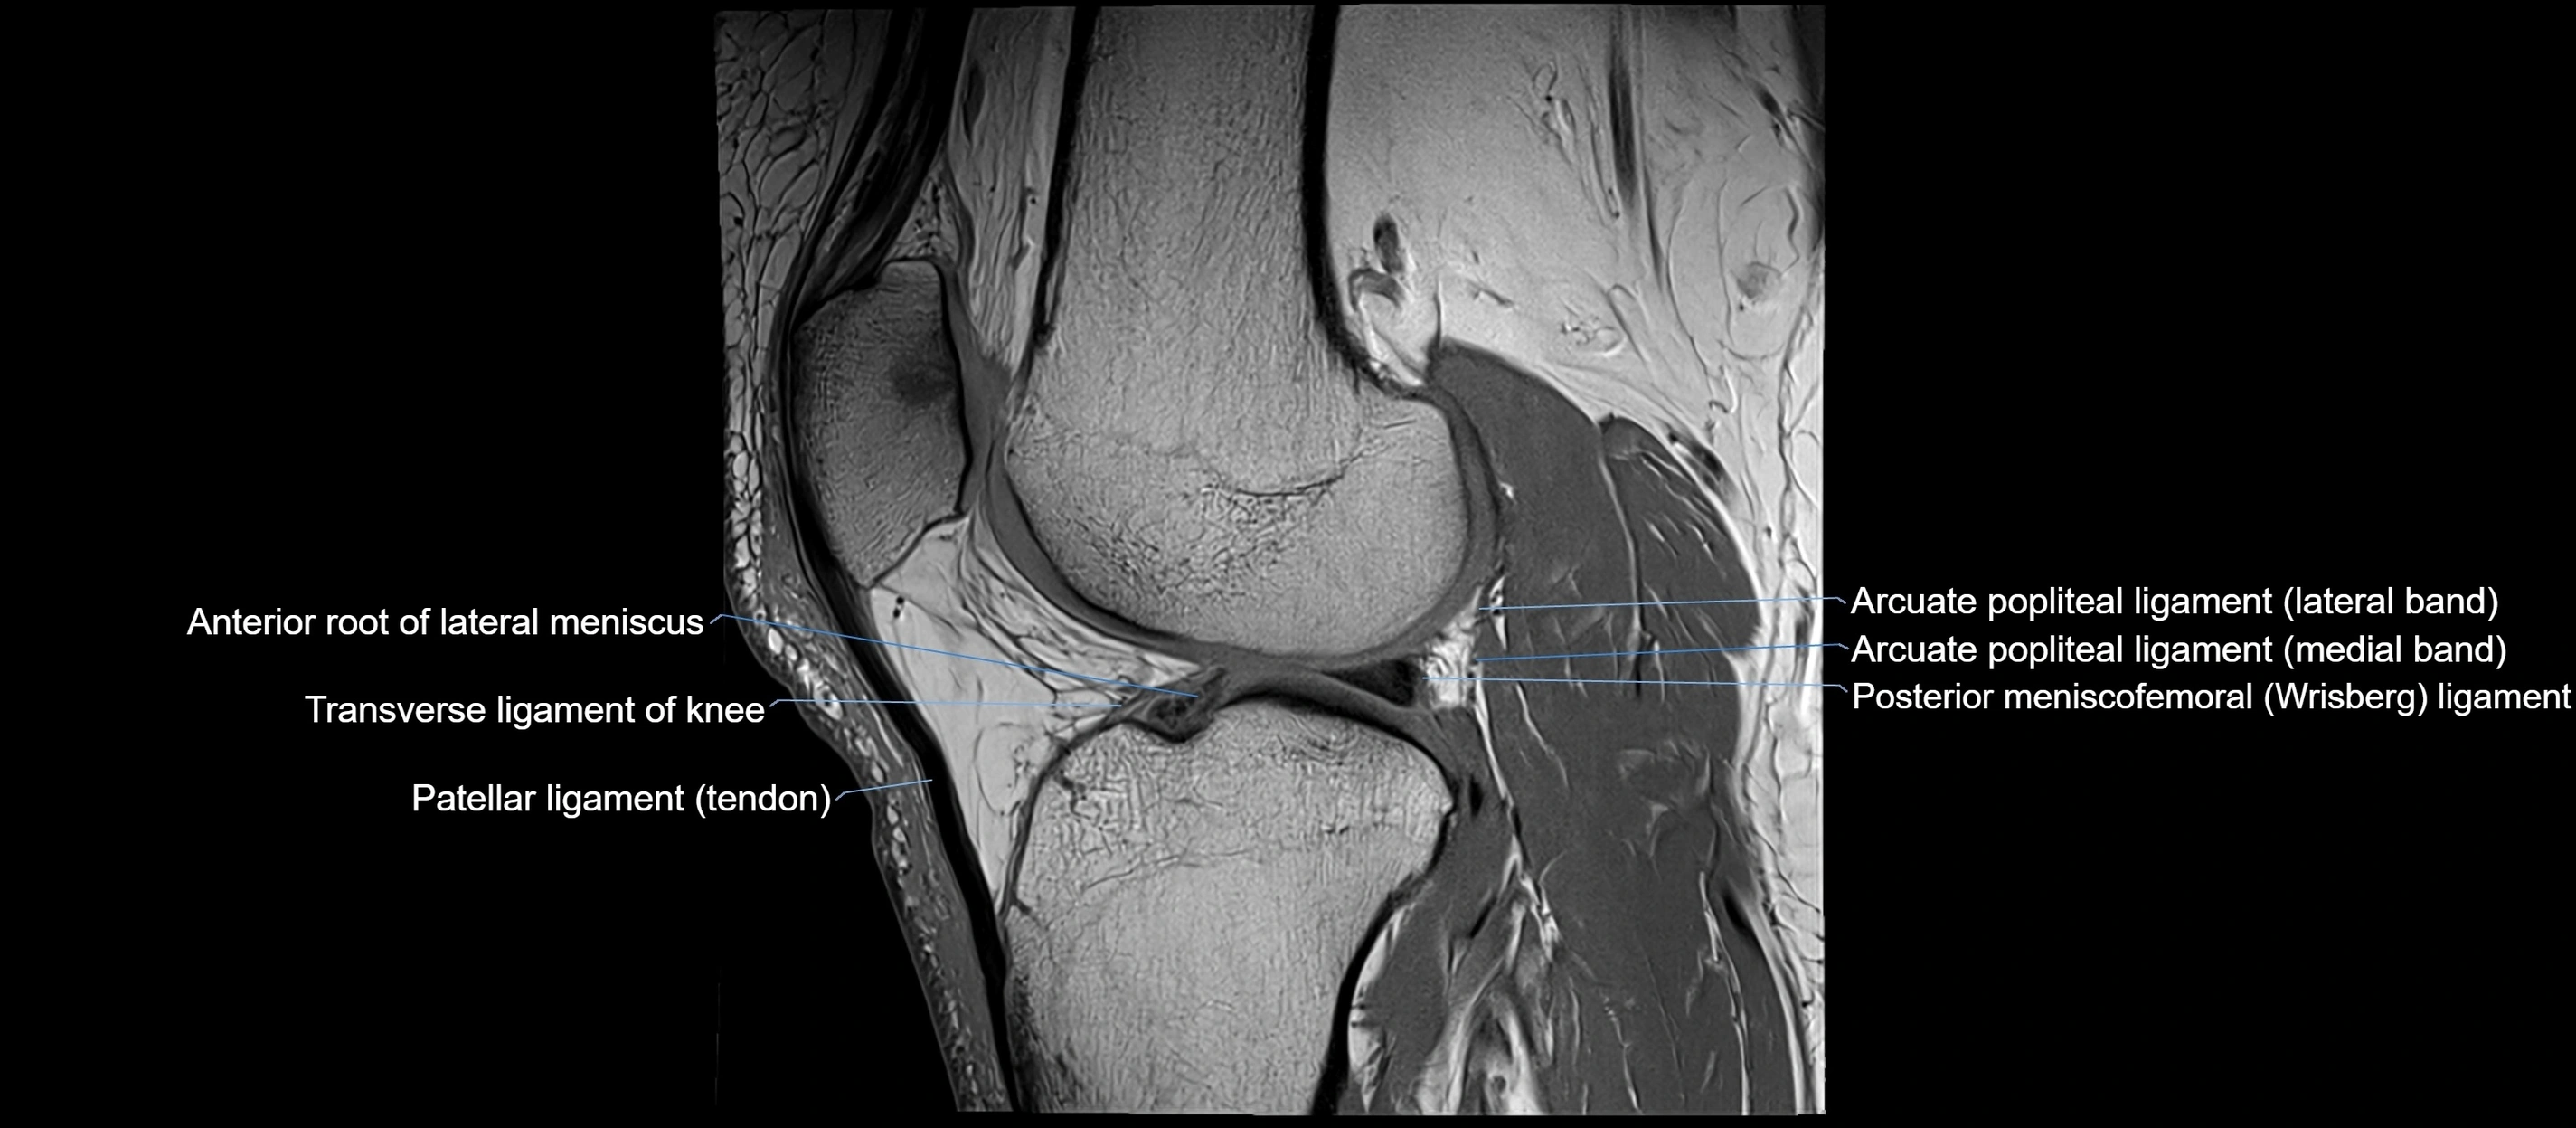

MRI images

image